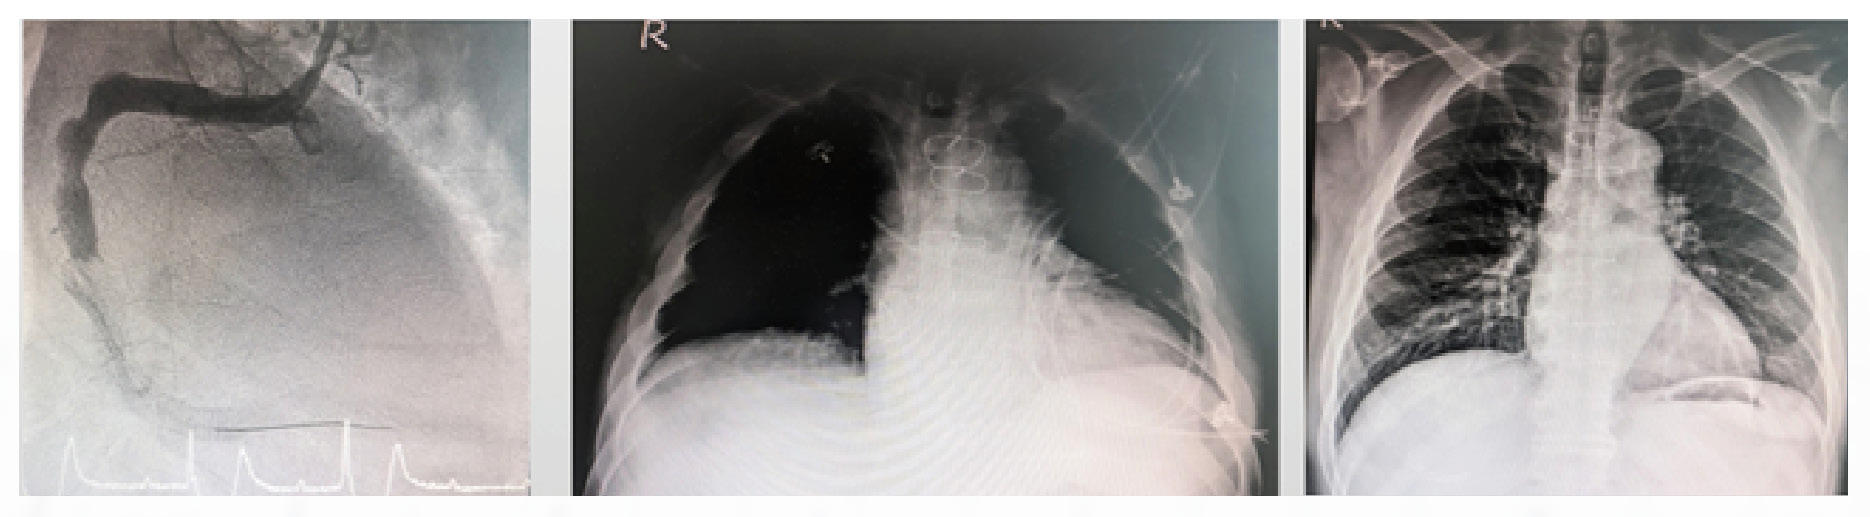

Dr. Hsiang-Yu Yang shared a recent case involving a 42-year-old male patient who was rushed to the hospital with an acute myocardial infarction (AMI). A cardiac catheterization revealed severe coronary artery obstruction. During the stenting procedure, the patient suddenly suffered a cardiac arrest.

The medical team immediately initiated Extracorporeal CPR (E-CPR) with ECMO support. Despite these efforts, the patient still developed severe cardiogenic shock and acute pulmonary edema.

The medical team promptly implanted the CentriMag Biventricular Short-term Ventricular Assist Device (BiVAD), successfully stabilizing the patient’s vital signs. During the subsequent course of treatment, the patient was first transitioned to a long-term Ventricular Assist Device (LVAD) and ultimately underwent a successful heart transplant. The patient has since recovered and been discharged from the hospital.

In another clinical case, a 53-year-old male patient suffered from right ventricular (RV) failure caused by an acute myocardial infarction. Despite receiving cardiac catheterization and coronary artery bypass grafting (CABG), his heart function failed to recover. The medical team subsequently implanted a CentriMag Right Ventricular Assist Device (RVAD) to provide circulatory support. This intervention successfully stabilized the patient while he awaited a heart transplant, which was eventually performed with great success. The patient has since fully recovered and been discharged.